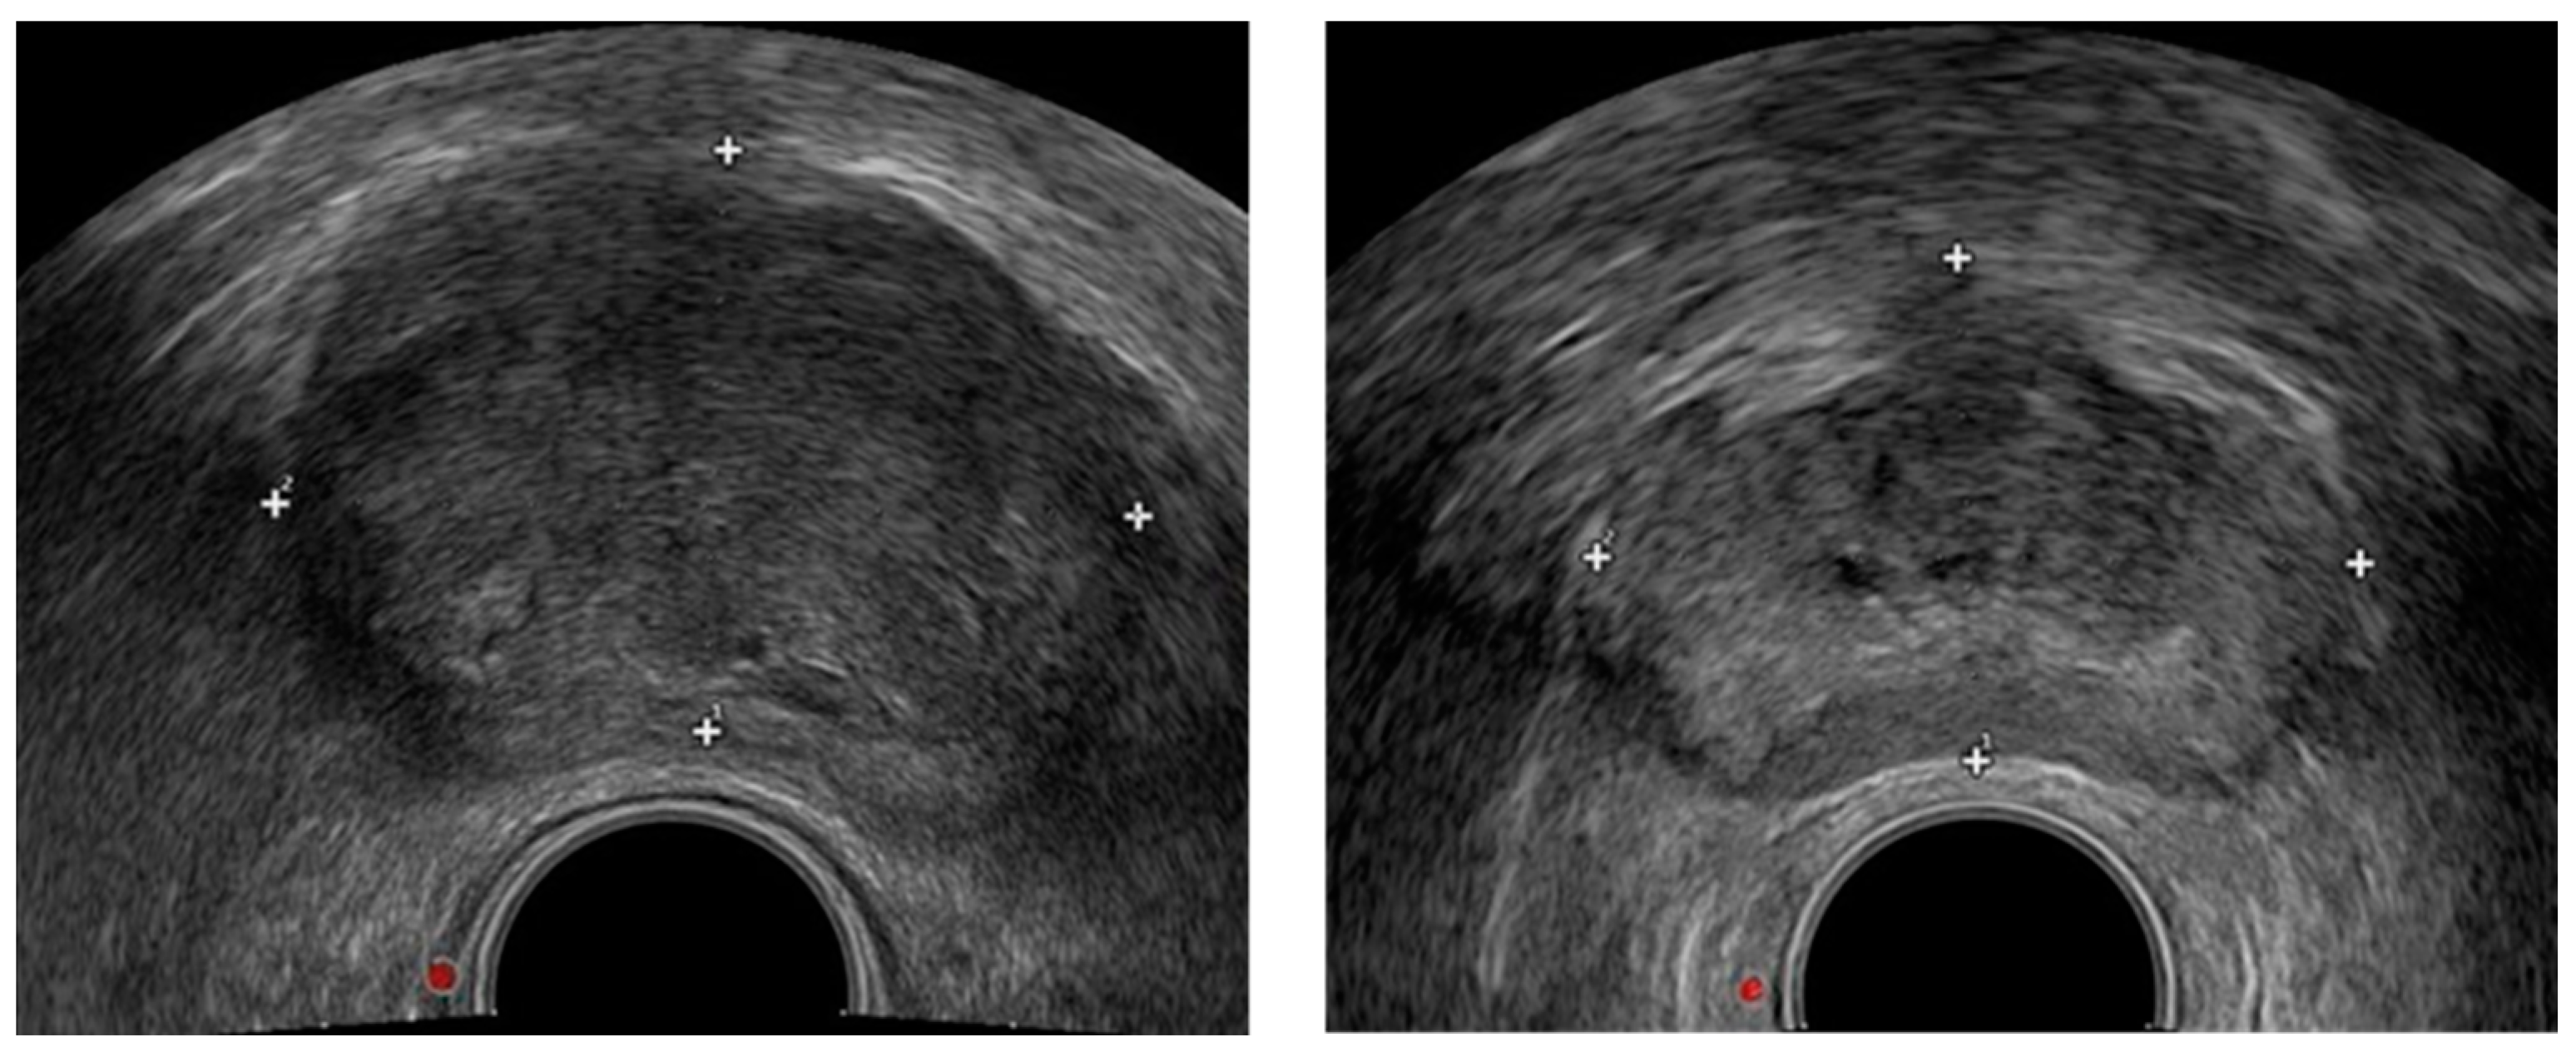

2.1. Data Preprocessing

3.1. Dataset